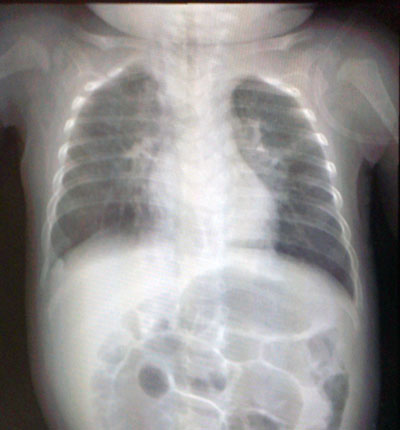

昨日撮ったX線写真。

炎症の白い影が減っている。

そして入院後に再度撮影した画像を見せて頂いた。

肺の上部が潰れている。 (←ロールオーバー有り)

かなり良くない状態であった。

つまり入院時はまだピークではなかったってこと。

ケッコー危ない状態だったんだな・・・。